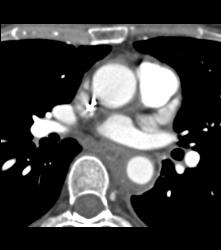

Left Anterior Descending Coronary Artery (LAD) and Right Coronary Artery (RCA) Disease